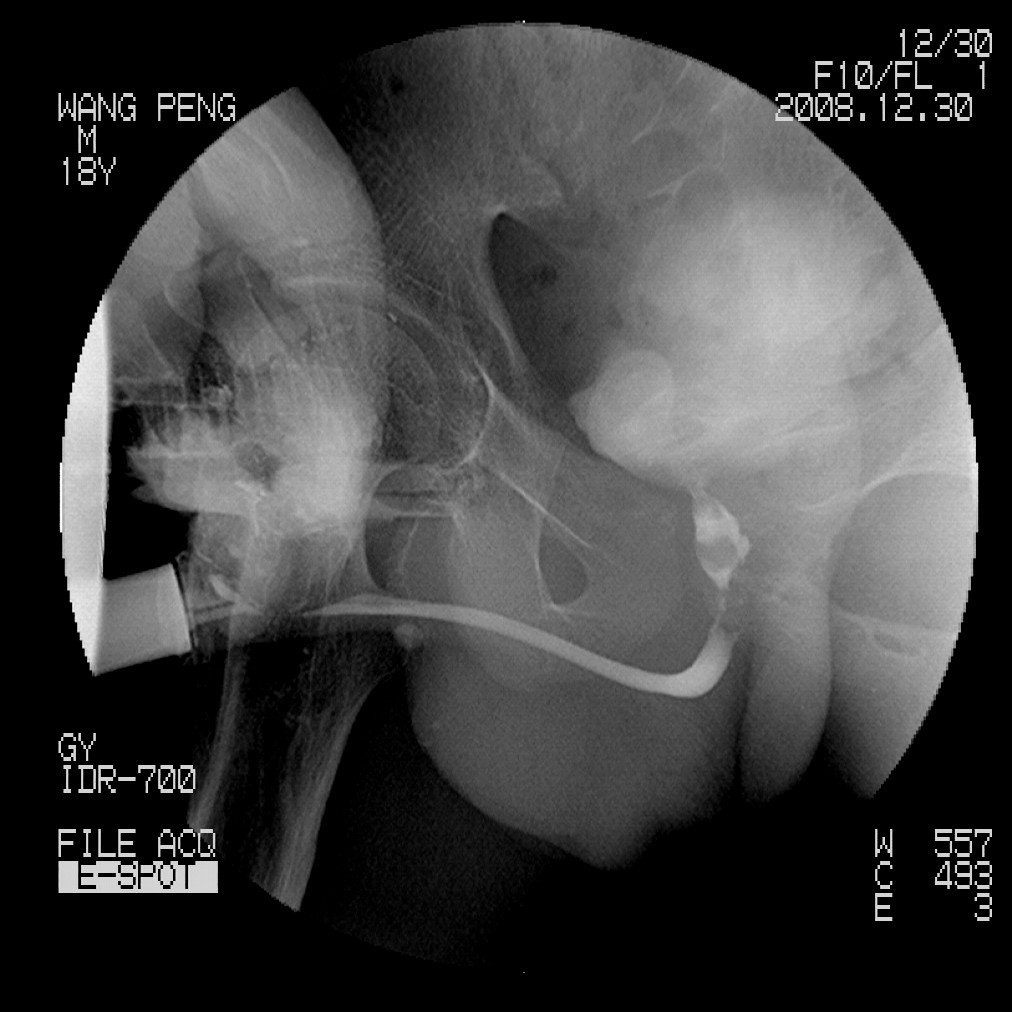

标题: X6910:经典的膀胱及尿道多发结石 [打印本页]

标题: X6910:经典的膀胱及尿道多发结石

患者,男,18岁,尿流不畅数月。

膀胱及后尿道多发结石,谢楼主分享

膀胱及尿道多发结石。

膀胱及后尿道多发结石,谢谢分享---------------------------